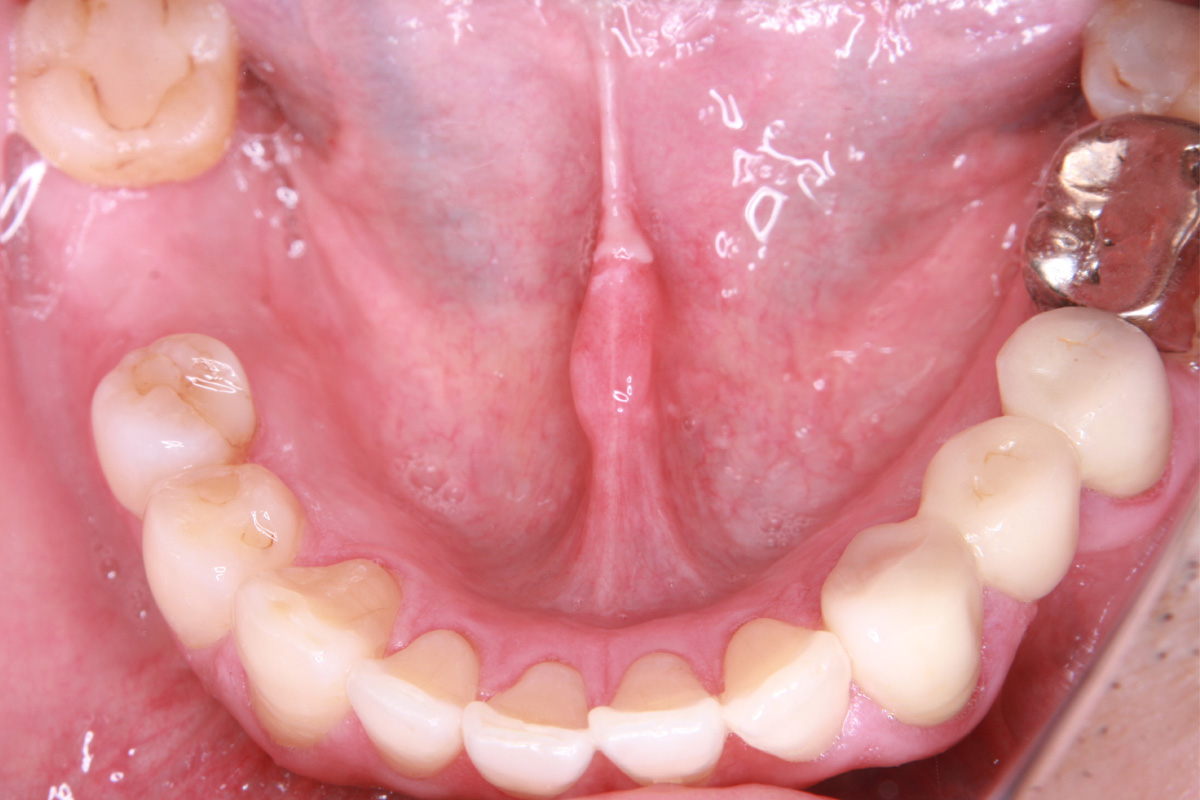

初診時

歯が割れていて、痛みがあり、抜歯となりました。

親抜歯後、歯ぐきは治癒しました。しかし、インプラント治療のためには骨が不足していました。

骨移植(人工骨+メッシュプレート)を行い、骨を造りました。

インプラント手術を行いました。

インプラント手術から3ヵ月後、型どりをして、仮歯を製作しました。

仮歯の調整期間を経て、セラミックの歯が入りました。

レントゲン画像 治療前 インプラント治療後

| 患者属性 | 50代 男性 |

|---|---|

| 主訴 | 右下の歯が痛い。(抜歯後は、インプラント治療希望) |

| 診断 | 右下第一大臼歯 歯根膜炎 |

| 治療期間・通院回数 | 骨移植~インプラント治療 約1年(来院10回程度) |

| 治療費 | 骨移植 77,000円(税込) インプラント治療434,500円(税込) |